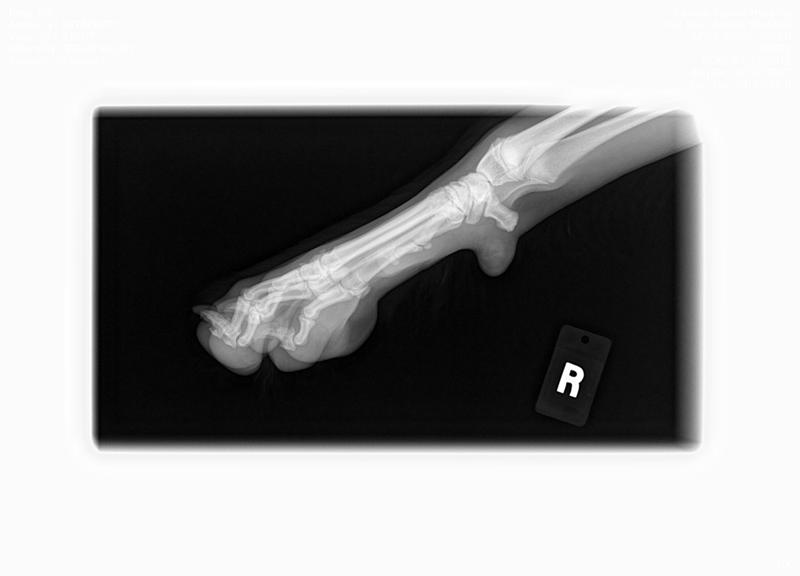

Here are BHRR's Spice's X-Rays: